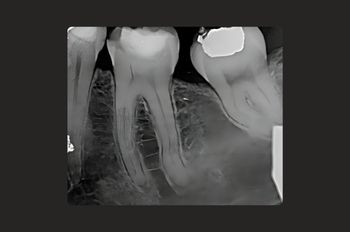

Our dentists here at Moltons Dental use the most up-to-date equipment to:

• Diagnose: We offer accurate and timely diagnoses.

• Act: Our gentle-handed dentists can remove the infection from the tooth using minimally invasive dental tools, a dental microscope, and state-of-the-art equipment.

• Prevent: We create protective and aesthetically pleasing crowns to restore the tooth’s appearance and functionality, thereby reducing the likelihood of further infections.

Our dentists are highly skilled in using cutting-edge technology to deliver long-lasting treatments that will secure your oral health for years to come.